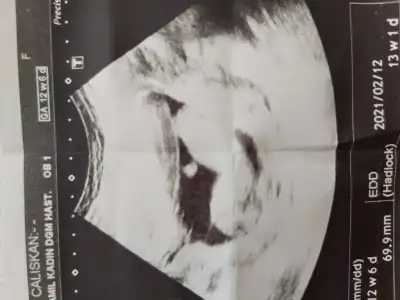

Bizede cinsiyet tahmininde bulunur musunuz?

Eklentiler

• 15982638652736534617085001185534.webp

15982638652736534617085001185534.webp

24,7 KB · Görüntüleme: 78

Burda kac 11 haftalik olmasi lazim

• 15982678976997957826004254294100.webp

15982678976997957826004254294100.webp

23,8 KB · Görüntüleme: 68